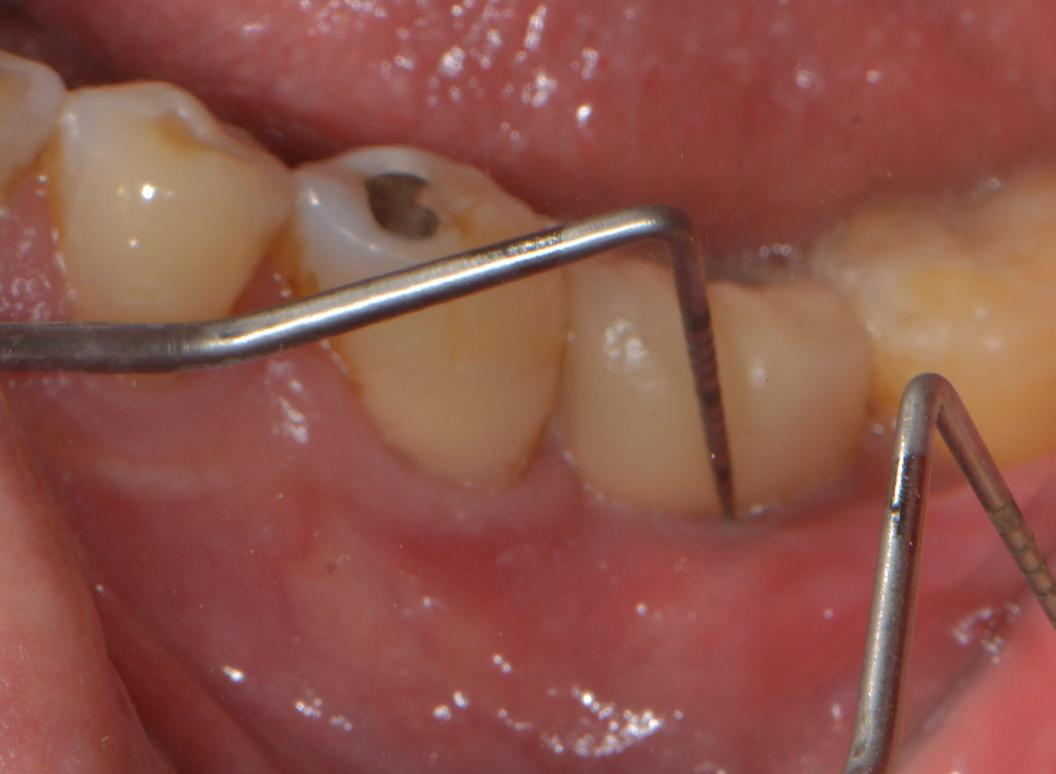

A 55-year-old woman presented for diagnosis of pain in the maxillary left posterior quadrant. About 1 year prior to that date, another endodontist had performed endodontic therapy on tooth 15. She had continued symptoms in the area. The endodontist checked tooth 15 and did not believe that her symptoms were related to that tooth, but he did not diagnose the source of her symptoms. On the day of my consultation, if she pushed laterally on tooth 15 with her tongue, she could elicit moderately sharp pain. She also had a constant ache in the area.

A periapical radiograph and a limitedfield-of-view cone beam computed tomogram of teeth 14 and 15 were taken, and no radiographic signs of apical periodontitis related to these teeth were noted that day (Fig 1). Sensibility tests were also performed. Tooth 15 responded normally to palpation and to bite and felt “different” on percussion (not painful, which is an important distinction to make). Tooth 14 responded

normally to palpation, percussion, and bite. Cold placed on tooth 14 triggered a significantly elevated, throbbing response that lingered more than 1 minute. Of all the tests performed, the cold on tooth 14 most closely replicated the pain of her chief complaint.

We reviewed treatment options, including no treatment. She elected to have endodontic therapy on tooth 14 performed that day. Local anesthetic was administered, and a dental dam was placed. This molar was slightly unusual in that I obtained patency in the palatal, distobuccal, and second mesiobuccal canals (MB2) that day, but the first mesiobuccal canal (MB1) was still not patent. Usually, it is MB2 that is the hardest to instrument. Calcium hydroxide medicament and a provisional restoration were placed. The patient was scheduled to return in 2 weeks for completion of endodontic therapy on tooth 14.

When she returned, I asked about her symptoms. The overall pain had reduced significantly, and the pain in tooth 15 with lateral pressure was gone, but there was still a deep ache in the area, now focused near tooth 15. She noticed a throbbing in the area with positional changes, such as sitting up and bending over. Sensibility tests were performed again. Tooth 14 responded normally to percussion, palpation, and bite. Tooth 15 responded normally to palpation, and percussion and bite elicited a moderately painful response (different from the results of the sensibility

tests performed preoperatively). We discussed the possible reasons for the pathosis related to tooth 15, including fracture. I recommended that if she desired to save the tooth, we should initiate retreatment of tooth 15 and place calcium hydroxide in the tooth. I would then see her a month later for a short consultation to check on her symptoms before obturating teeth 14 and 15. She agreed to this treatment plan.

Orthograde retreatment of tooth 15 was initiated that day in the usual manner, and calcium hydroxide was placed. At the follow-up appointment 1 month later, she was happy to report that

all her symptoms had resolved and that she had not needed to take ibuprofen or acetaminophen for more than 2 weeks. Both teeth were tested that day, and both responded normally to percussion, palpation, and bite. We then scheduled her for completion of treatment of both teeth.

At our final appointment, I was able to fully instrument the MB1 canal. The final postoperative radiograph shows the curvature of the MB1 canal of tooth 14 (Fig 2). The teeth were closed with a medicated sponge and provisional material, and the patient was referred back to her general dentist for restoration of these teeth.

Fig 2. Postoperative radiograph of teeth 14 and 15.

Fig 1. Preoperative radiographs. A. Tooth 14. B. Tooth 15.